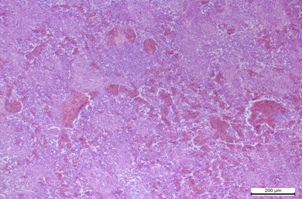

При стафілококової септицемії характерними є некрози та судинні розлади у багатьох паренхіматозних органах, включаючи печінку, селезінку, нирки і легені.

Рис. 9. Селезінка. Гостра застійна гіперемія, атрофія лімфоїдних фолікулів. Гематоксилін та еозин. х 200